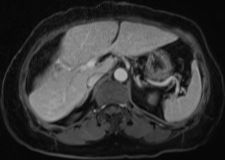

結腸腫瘤概述

結腸腫瘤是指發生在結腸部位的腫瘤,可分為良性和惡性,結腸腫瘤早期癥狀不明顯,隨著病情發展,可能出現腹痛、便血、腸梗阻等癥狀,治療方法包括手術、化療、放療等,具體治療方案需根據患者的具體情況制定。